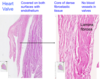

zoomed-in, heart valve

heart valve